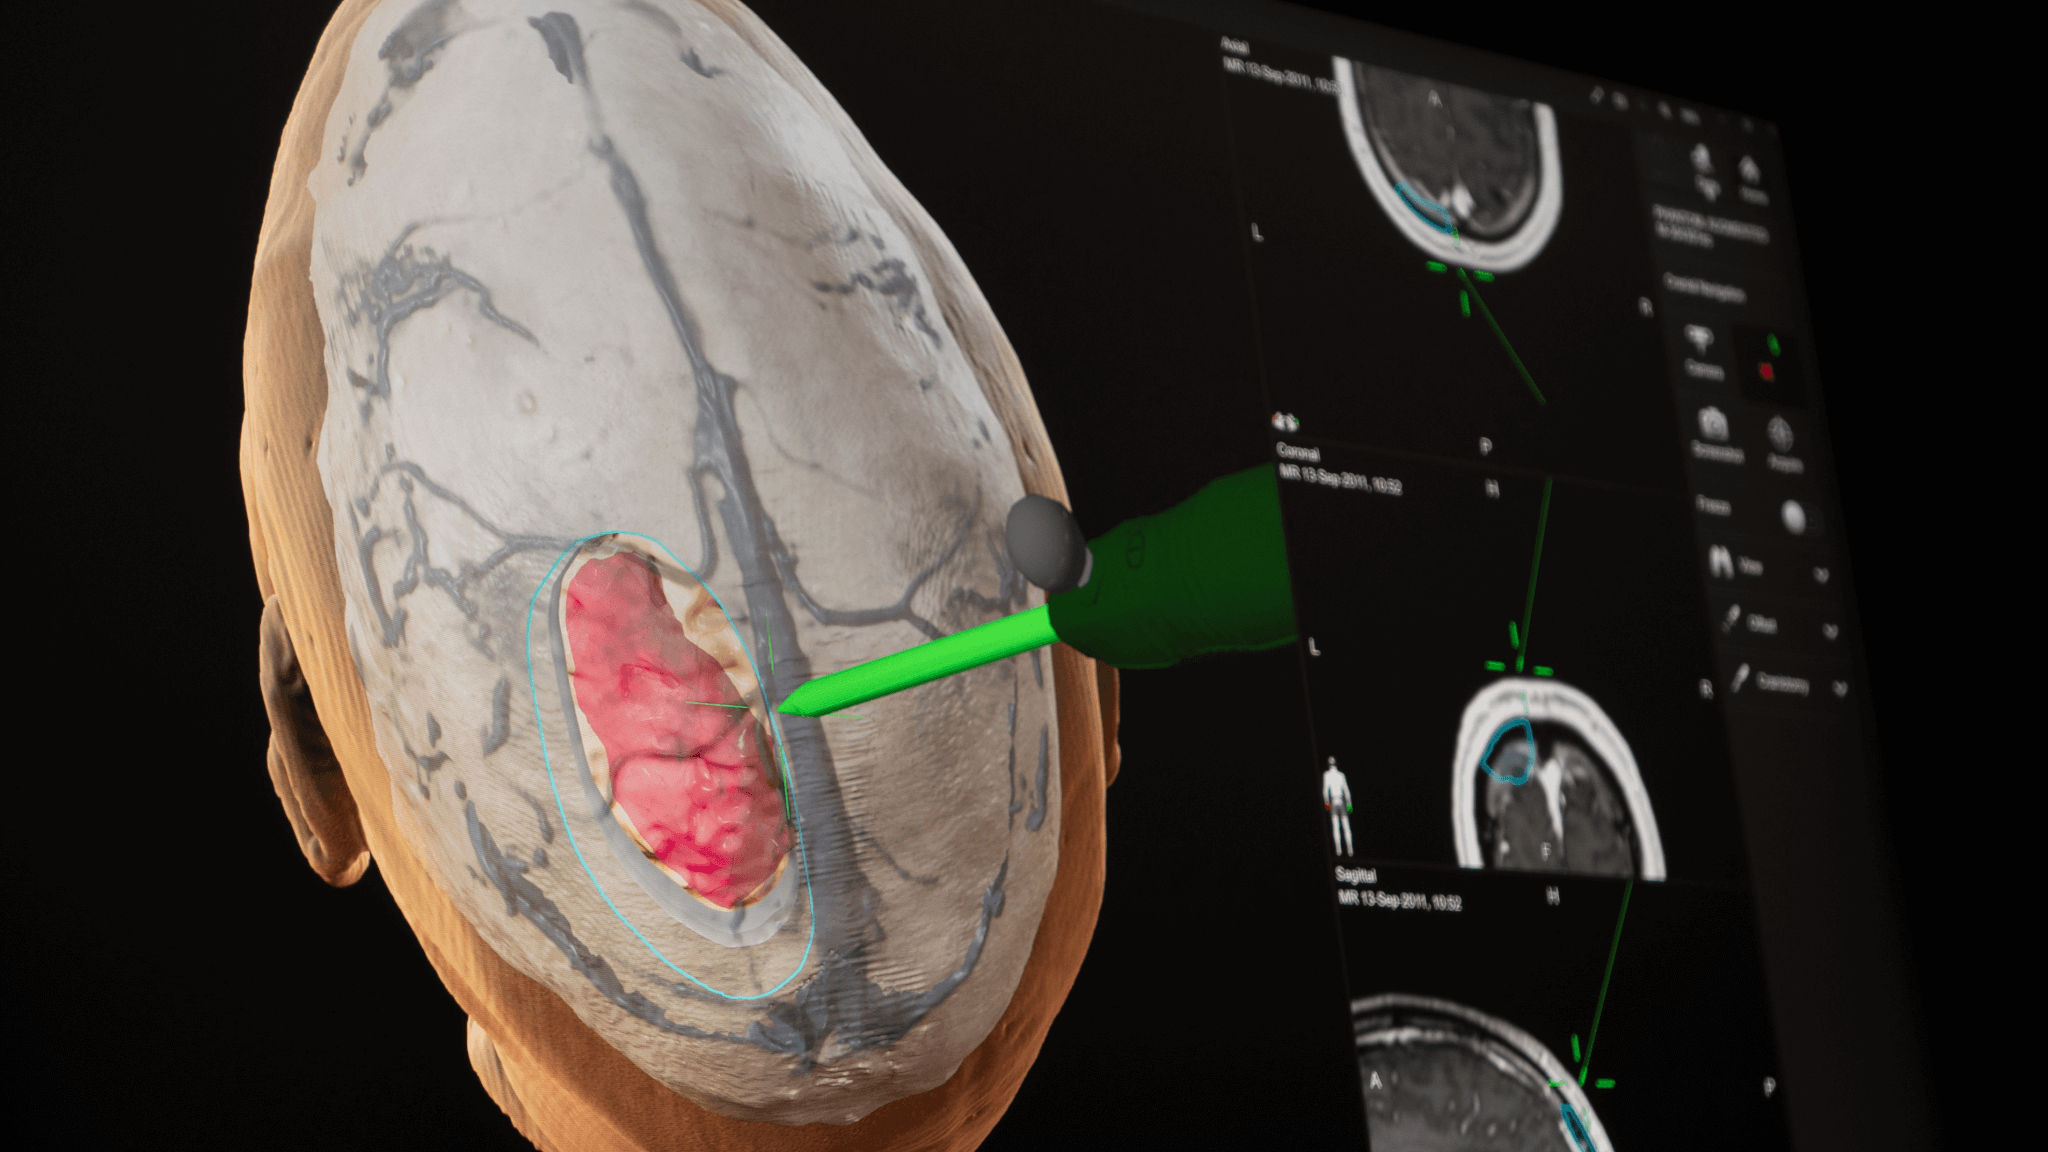

Brainlab neuronavigation combines ease of use with extended functionality tailored to surgeons’ needs